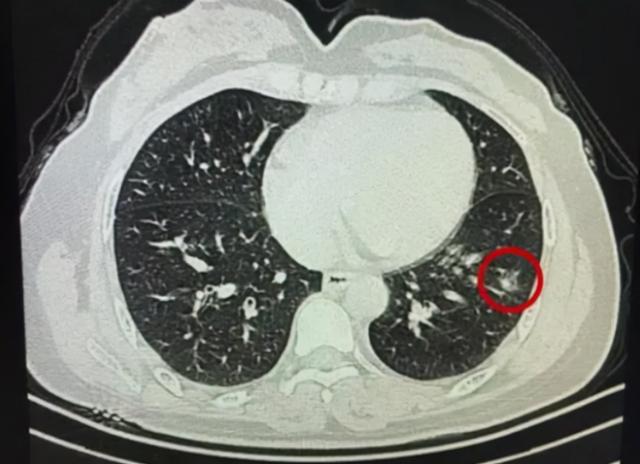

体检时CT监测、血常规检测、肺动脉监测等检查方式可以清楚患者机体的潜在病灶,机体的各项部位产生结节是检测单最常见的一种病症,而在体检项目当中通过检测仪器观察部位的病灶是预防癌症的主要机制。

机体部位常见的结节病灶最常见的有:甲状腺结节、肺部结节、乳腺结节等临床病变,而随着检测仪器判断结节处于疾病的阶段,从而制定出饮食结构与药物的改变来预防癌症的转变几率。

临床上又针对部位的结节做出相关的研究,通过体检数据监测初次体检,患肺结节的概率达到15%~28.9%,患甲状腺结节的概率达到35.8%~46.7%,患乳腺结节的概率达到29%~32.2%。